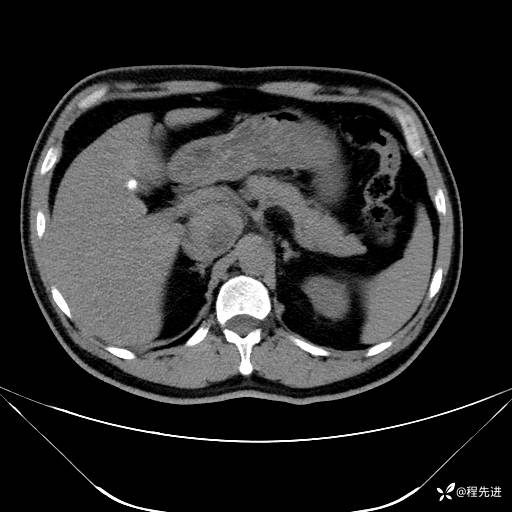

【腹盆】特别精彩病例|发现腹膜后肿物1月余

患者性别:男

患者年龄:42岁

主诉:发现腹膜后肿物1月余

现病史:患者1月余前查体,行超声检查提示:后腹膜囊实性肿块;慢性胆囊炎伴胆囊内结石;无腹痛腹胀,不伴腹泻发热等;偶感腰背部酸痛。

CT平扫+增强: